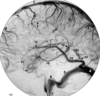

1 internal carotid artery - cervical segment

2 internal carotid artery - vertical petrous segment

3 internal carotid artery – horizontal petrous

segment

4 presellar segment (C5) internal carotid artery

9 ophthalmic artery

10 and 11 supraclinoid segment internal carotid artery

13 anterior choroidal artery

14 internal carotid artery bifurcation

15 A1 segment of anterior cerebral artery

16 medial lenticulostriate arteries

17 recurrent artery of Heubner

18 A1-A2 junction anterior cerebral artery